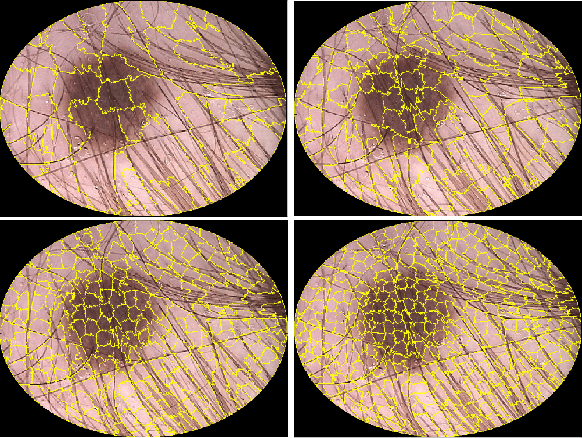

Abstract:We present a superpixel-based strategy for segmenting skin lesion on dermoscopic images. The segmentation is carried out by over-segmenting the original image using the SLIC algorithm, and then merge the resulting superpixels into two regions: healthy skin and lesion. The mean RGB color of each superpixel was used as merging criterion. The presented method is capable of dealing with segmentation problems commonly found in dermoscopic images such as hair removal, oil bubbles, changes in illumination, and reflections images without any additional steps. The method was evaluated on the PH2 and ISIC 2017 dataset with results comparable to the state-of-art.